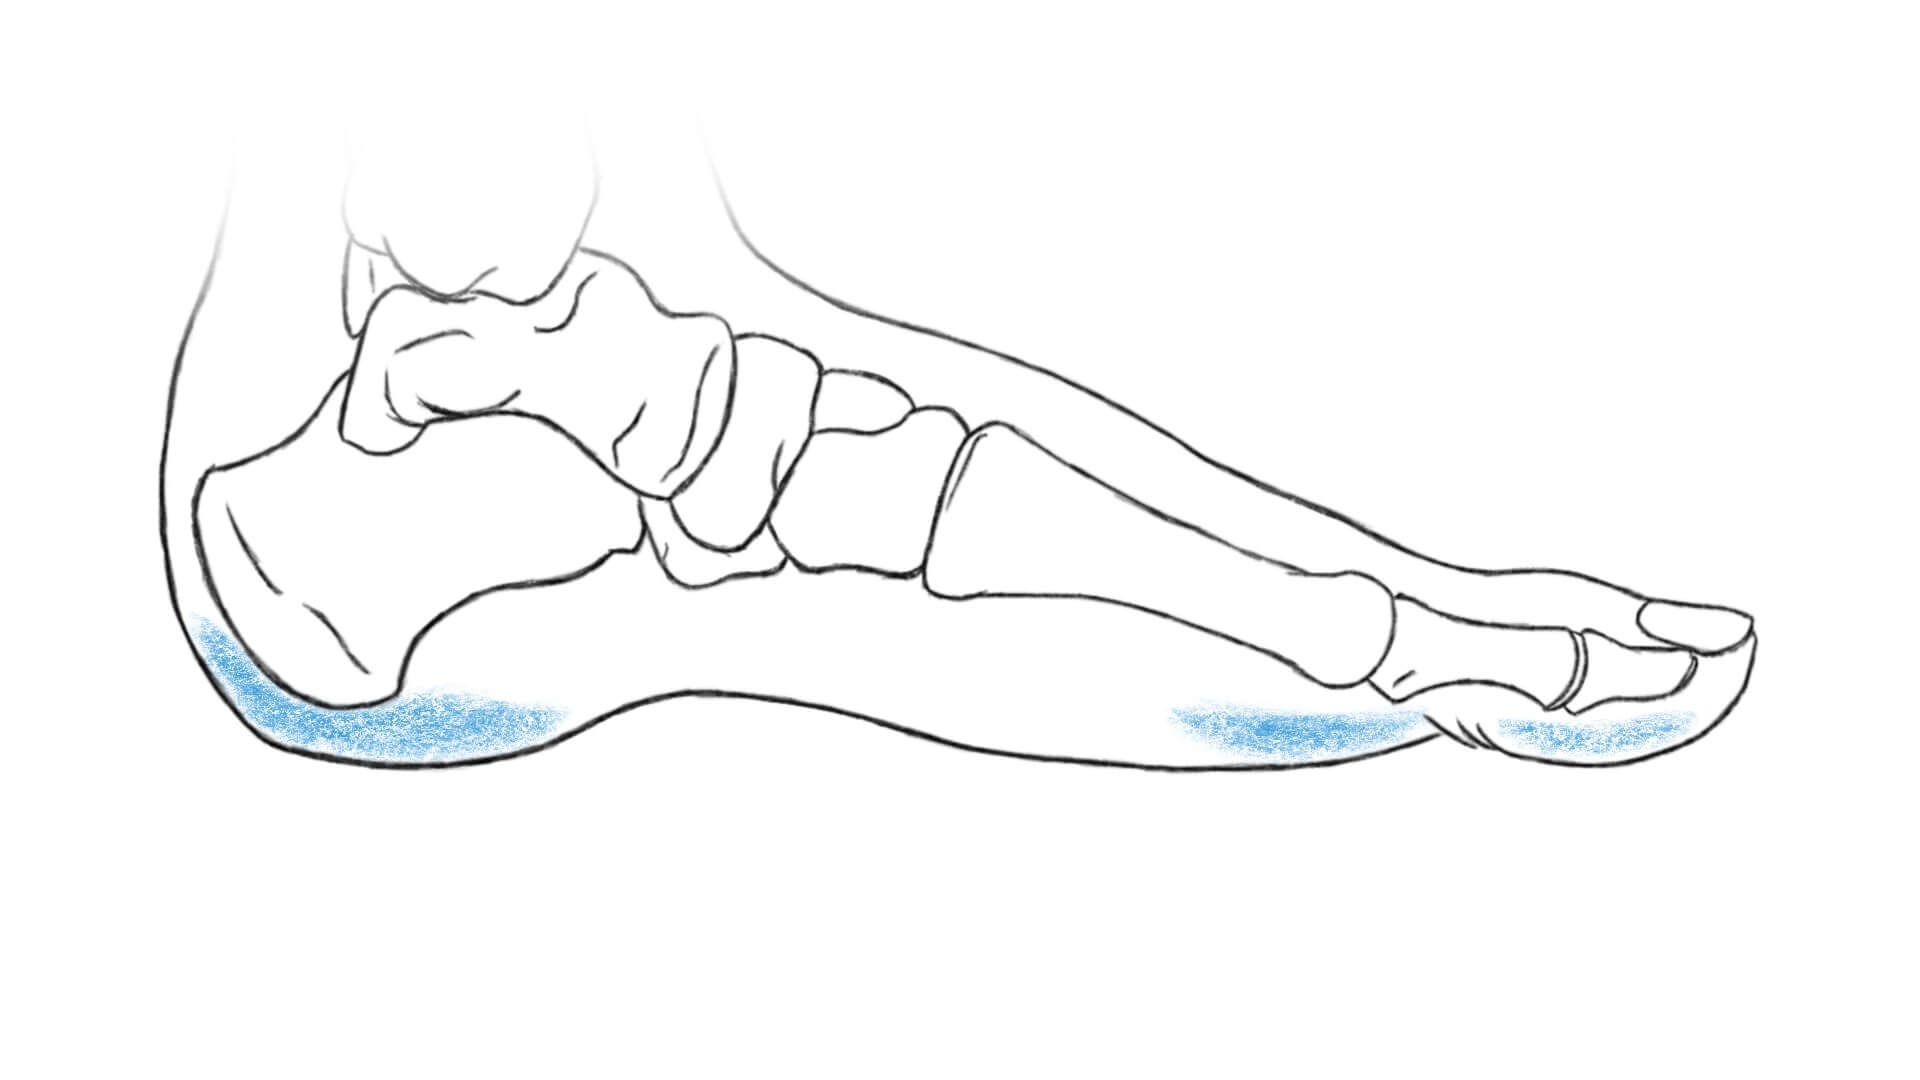

Unter der Haut unserer Fußsohle befindet sich ein ca. 2 cm dickes Fettpolster. Man kann es sich wie ein prallgefülltes Wasserkissen vorstellen. Es dient dazu den Druck, der besonders hoch an der Ferse und am Groß- und Kleinzehenballen ist, auf eine größere Fläche zu verteilen. Das Fettpolster wirkt also wie ein Stoßdämpfer. Außerdem trägt es durch seine Festigkeit auch zur Stabilität des ganzen Fußes bei. Durch häufiges langes Stehen oder starken Gewichtsverlust kann dieses Polster schrumpfen. Das führt dazu, dass der Druck nicht mehr so gut verteilt werden kann und dadurch lokal sehr großer Druck entsteht. Das kann zu starken Schmerzen in der Fußsohle führen.

Das Fußgewölbe

Da das Fußgewölbe eine sehr wichtige Funktion für unseren aufrechten Stand und unsere Fortbewegung übernimmt, wollen wir es uns hier genauer anschauen.

Es befindet sich zwischen der Ferse und dem Großzehenballen. Das Fußgewölbe federt Stoßkräfte ab, die auf unseren Körper einwirken. Stoßkräfte werden erzeugt, wenn das Gewicht unseres Körpers auf den Untergrund trifft. Umso härter der Boden ist, desto stärker die Kräfte. Treffen unsere Füße auf den Boden wird die Stoßkraft über unseren Rückfuß und Mittelfuß verteilt. Das Fußgewölbe hält dabei wie eine Feder dagegen. Am bildhaftesten ist dieser Mechanismus, wenn wir springen und dabei immer wieder mit den Füßen auf dem Boden „aufprallen“. Man stelle sich vor, die Füße wären komplett platt. Dann würden wir einfach auf den Boden „stoßen“ oder „platschen“. Durch das Fußgewölbe, welches zugleich fixiert und federt können die Stöße abgedämpft werden, ohne dass wir unser Gleichgewicht verlieren. Für die Stoßdämpfung sind noch weitere Strukturen in unserem Körper wichtig, vor allem die Bandscheiben in unserer Wirbelsäule.